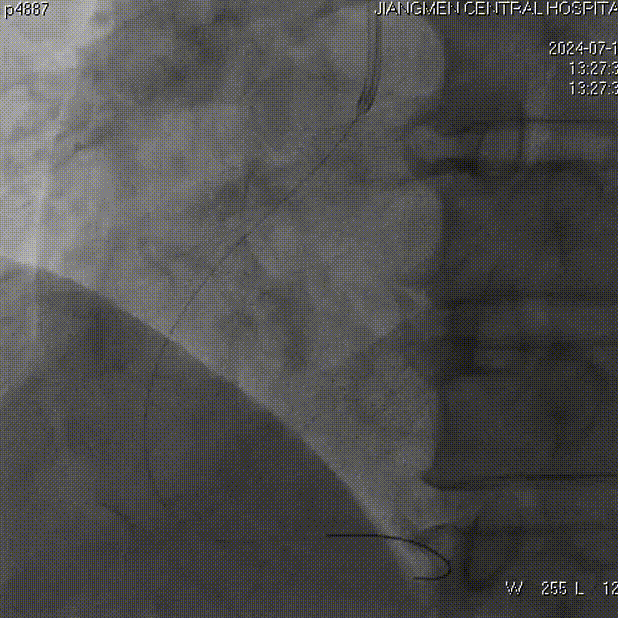

抽吸【例】量|【兑】话血栓抽吸